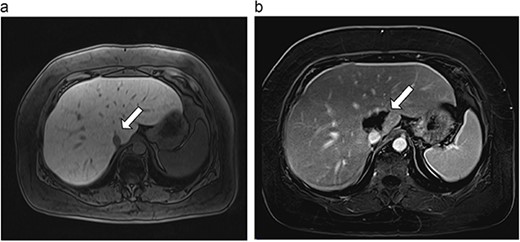

Six patients with six primary or secondary tumors of the caudate lobe were identified (Table 1). Median age at diagnosis was 68 years (51–77 years); two patients were female. Primary disease process was colon adenocarcinoma (n = 4; Figs 3–6), hepatocellular carcinoma (HCC; n = 1; Fig. 7) and metastatic pancreatic neuroendocrine tumor (n = 1; Fig. 8). All patients with colon adenocarcinoma received systemic therapy with 5-fluorouracil, oxaliplatin, and leucovorin (FOLFOX) prior to microwave ablation of hepatic metastases. The patient with metastatic neuroendocrine tumor had progression of hepatic metastases on lanreotide prior to microwave ablation. The patient with HCC had previously been treated with transarterial embolization and cryoablation of tumors, but had recurrence of disease, which was managed with microwave ablation.

| 3 (5a,b) | 68, F | Colon adenocarcinoma | 6 cycles modified FOLFOX-6 | 8 | Laparoscopic microwave ablation and low anterior resection of colon | 5 | 36.2 | 31.2 | 15 | No |

(a) Pre-ablation MRI demonstrating 5 mm lesion in caudate lobe of liver. (b) Post-ablation MRI (19 days postoperatively) demonstrating 36.2 mm complete ablation of caudate lesion.